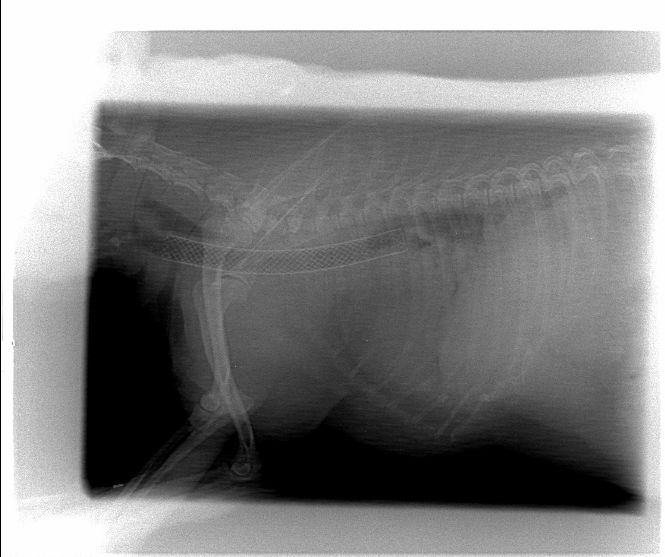

Lateral thoracic radiograph showing postoperative appearance of deployed intra-tracheal stent